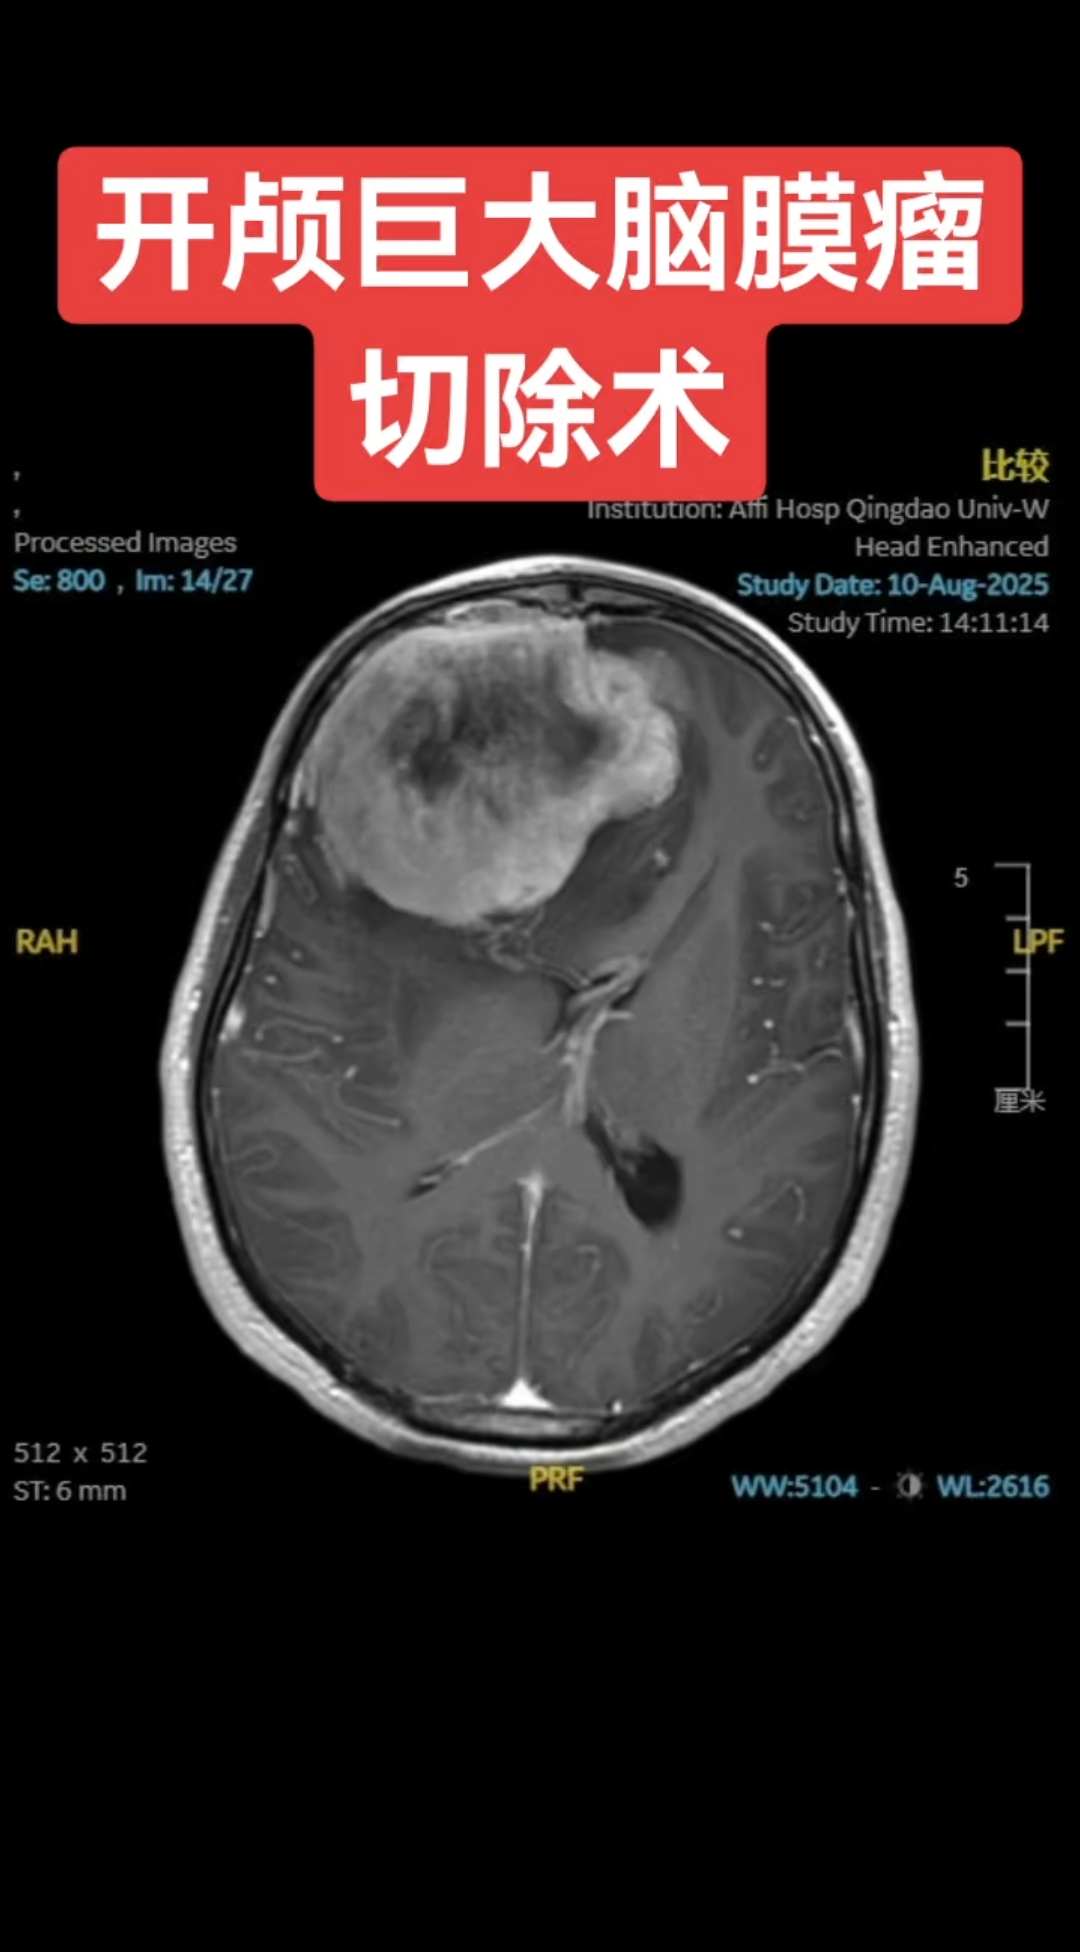

脑膜瘤手术通常需要开颅,但在特定情况下可以考虑非开颅治疗1 开颅手术 主要治疗方式开颅手术是脑膜瘤的主要治疗方式之一,特别是对于大多数脑膜瘤患者,开颅手术可以切除肿瘤,达到治愈的目的 适用情况当脑膜瘤位置相对表浅,与周围组织结构粘连不紧密时,开颅手术是首选的治疗方案2 非开颅。